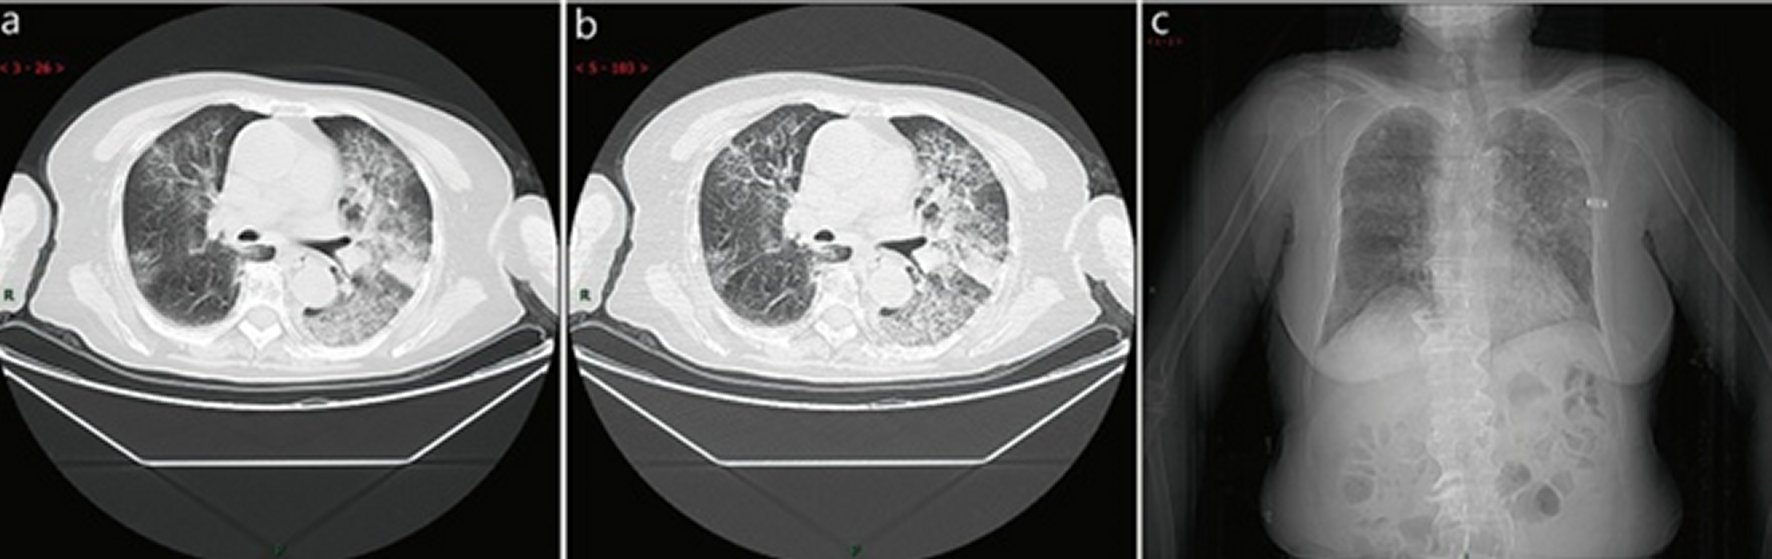

Матовое Стекло В Легких Фото